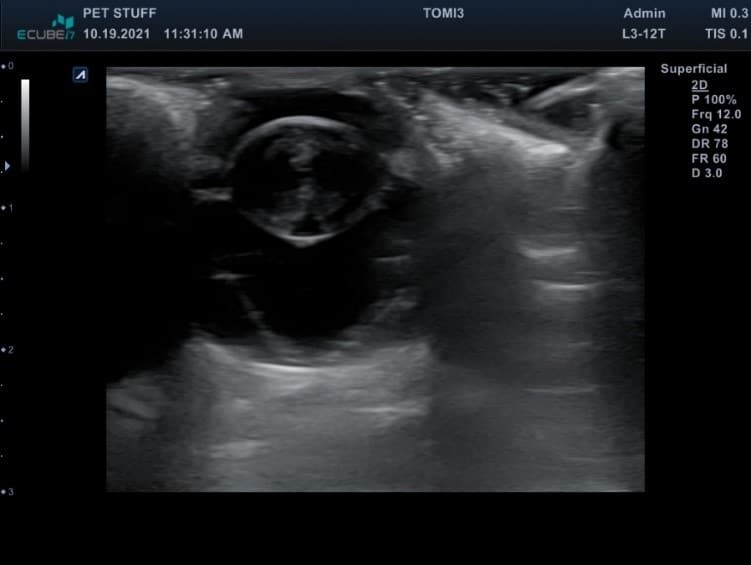

Depending on the results of the tests described above, it is possible to recommend further tests that can be performed within the hospital at the time of consultation or later. For example, if the direct evaluation of the eye or orbit is not possible, it is used Eyeball. The procedure is painless, most patients collaborate. This is thus achieved important details relating to the crystalline, vitreous, retina body, in the presence of tumor formations, orbital abscesses, etc.

Eye Ultrasound – Cataract of the Retina and Take -Off (Own Source)